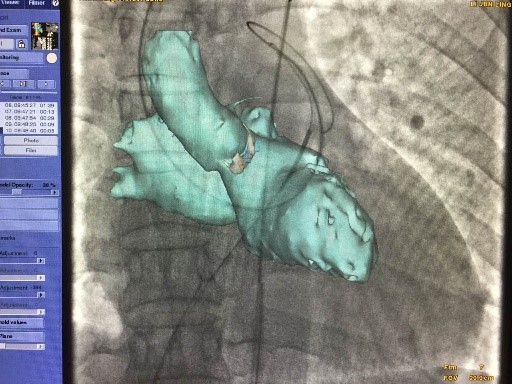

在房间隔缺损的患者中,行介入封堵术常常需要先行右心导管检查,以确定房间隔缺损的形态和大小。另需要依据造影测量的缺损直径选择封堵器的规格,封堵器释放过程中需要通过术者手感、透视和超声来确定封堵器的位置,以确保无残余分流。 GE 心脏高级解决方案可依据患者术前 CT 重建心脏3D解剖结构,术前可测量缺损直径和规划缺损路径,术中实时引导封堵手术,提高手术精度 具体操作步骤如下: (1)术前规划:DSA直接处理CT数据 一键提取心室和心房3D模型, 并规划房间隔路径

(2)术中智能3D实时引导封堵器释放,融合影像与心跳/呼吸同步--可精 确引导,降低风险,减少造影剂的用量,缩短手术时间